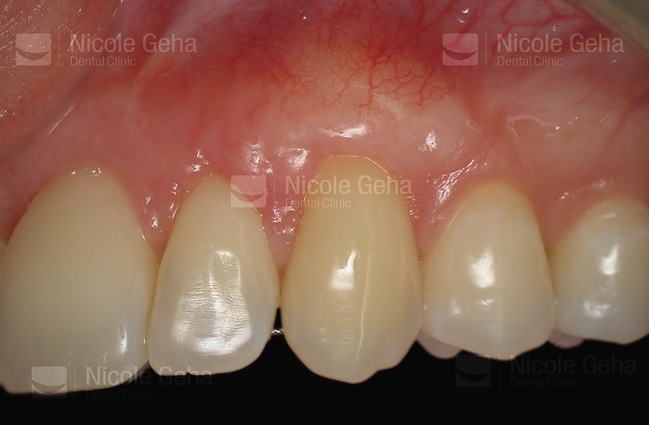

case 1: after